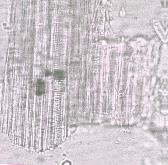

المقطع العرضي للورقة يبين وجود أدمة (Cuticle) سميكة تغطي خلايا البشرة ذات الجدر الرقيقة وهي خلايا مستطيلة بشكل واضح ونوعا ما تتخذ شكل المربع في أبعادها الضيقة ولذلك فإن خلايا النسيج الحشوي للبشرة (برنشيما) تبدو وكأنها مرتبة بشكل متوازي. الثغور بيضاوية الشكل وتتواجد بين الخلايا المجاورة في مواقع أبعادها الضيقة. خلايا النسيج العمادي لها أحجام مختلفة ويظهر أن النسيج مكون من طبقتين ولكن الخلايا متجاورة وغير متضامة. خلايا النسيج الوسطي الإسفنجي غالباً ما تكون مدورة الشكل، وتختلف أيضاً من حيث الحجم، غير متضامة. وخلايا النسيج الوسطي الإسفنجي توجد بها الحزم الوعائية والتي تضم الأوعية اللولبية والحلقية السميكة، بالإضافة إلى خلايا النسيج الحشوي (برنشيما) ذات الشكل المستطيل وتكون مصاحبة للأوعية والألياف. وكذلك تحتوي خلايا تحتوي النسيج الوسطي الإسفنجي على خلايا معينة (ايديوبلاستات) متناثرة وشكلها دائري إلى إهليجي وبلورات أكسلات الكالسيوم الإبرية الشكل المتواجدة في شكل حزم، كما يضم النسيج أيضاً أشكالاً مستطيلة تظهر كأنها قنوات لها نهايات مدببة وتمتلئ بمحتويات تتراوح ألوانها بين الأصفر والبرتقالي. خلايا بشرة الساق عبارة عن خلايا نسيج حشوي (برنشيما) مستطيلة الشكل. وتحتوي الأجزاء الداخلية من الساق على خلايا نسيج حشوي مستطيلة إضافة إلى الحزم الوعائية الليفية المتراصة والتي تضم القصيبات التي بها نقرات على جوانبها والأوعية الكبيرة الحجم ذات الترسبات الحلقية واللولبية والشبكية. بعض خلايا النسيج الحشوي (برنشيما) الكبيرة الموجودة بالساق ممتلئة تقريبا بمحتويات ذات لون بني يميل للون البرتقالي. (DPS ZCHRTM Unpub. Result).

- (أ) منظر سطحي لجزء من الورقة يبين خلايا البشرة المتطاولة بشكل ملحوظ والمتواجد بصورة متوازية بجوار بعضها وتتواجد الثغور البيضاوية الشكل بين الخلايا المتجاورة في مواقع أبعادها الراسية الضيقة المربعة الشكل.

- (ب) جزء من الأنسجة الوعائية للورقة تبين أوعية متلاصقة ذات ترسبات حلقية ولولبية والتي تجاورها أيضا أليافها المصاحبة القصيرة.

- (ج) جزء من الساق تبين الحزم الوعائية الليفية المتراصة وهي تشمل القصيبات التي بها نقرات على جوانبها والأوعية الكبيرة التي توجد بها ترسبات حلقية أو لولبية أو شكلية. (الصورة مكبرة 250، 400، 250 مرة على التوالي).